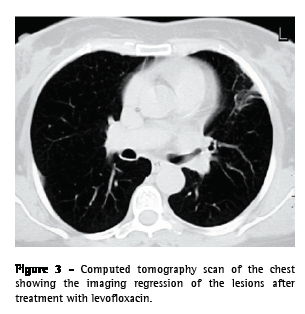

From the analytical study, we highlight the following results: an erythrocyte sedimentation rate of 98 mm in the first hour; a cancer antigen 125 level of 63.3 U.mL-1 (<35.0); a carcinoembryonic antigen level of 3.55 ng.mL-1 (<2.5); and a slight increase in the C-reactive protein level. The serum immunological study, the viral marker analysis, and the final analytical study revealed no other significant alterations. The results of colonoscopy, transabdominal pelvic ultrasound, mammography, and cervicovaginal cytology were normal. The first fiberoptic bronchoscopy performed showed diffused signs of inflammation at the level of the lingula. The cytological examinations of aspirate, bronchial lavage, and bronchoalveolar lavage were negative for neoplastic cells. Microbiological analysis under anaerobic conditions also yielded negative results, as did testing for acid-fast bacilli. The patient was then submitted to transthoracic needle aspiration biopsy (TNAB), which, in the extemporaneous cytological examination, showed an inflammatory process with suppuration. In view of this provisional result, antibiotic therapy with oral levofloxacin 500 mg daily was initiated, and it was decided that a second fiberoptic bronchoscopy should be carried out. However, the cytological examination of the TNAB revealed morphological aspects consistent with the presence of Actinomyces, confirmed through microbiological culture analysis of the bronchial and bronchoalveolar lavage of the second fiberoptic bronchoscopy, in which A. naeslundii was identified (Figure 2). Testing for acid-fast bacilli yielded negative results. Due to the clinical and radiological improvement after a month of treatment (Figure 3), we opted to maintain the antibiotic therapy already initiated, altering the dose schedule: intravenous levofloxacin (500 mg/day) for four weeks and oral levofloxacin (500 mg/day) thereafter. There were no adverse drug effects, and the treatment was continued for 16 weeks, until there was complete radiological normalization. Analytically, we observed a decrease in the erythrocyte sedimentation rate and in the initially altered levels of both tumor markers, as well as normalization of the C-reactive protein level. The patient was also submitted to dental treatment.